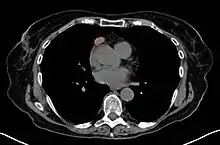

كثيرا ما يجرى الصدر بالأشعة السينية كثيرا ما يكون أداؤها، بل قد يشير إلى تشخيص بديلة (على سبيل المثال، لامبرت ايتون بسبب ورم في الرئة) والاعتلال المشترك. فإنه يمكن أيضا تحديد اتساع منصف (تشريح) توحي ورم الغدة الزعترية، ولكن الصور المقطعية أو التصوير بالرنين المغناطيسي (التصوير بالرنين المغناطيسي) تكون أكثر حساسية لتحديد سبل thymomas، وبصورة عامة القيام به لهذا السبب.[12]